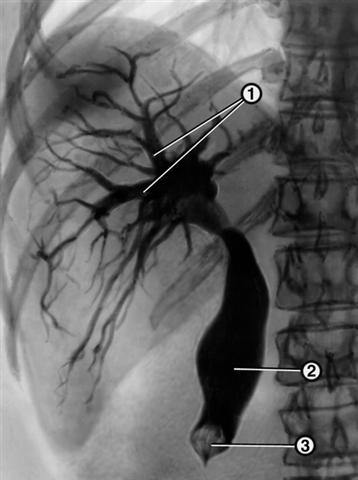

Рис. 1. Рентгенограмма, полученная при чрескожной чрезпеченочной холангиографии у больного желчнокаменной болезнью: желчные протоки (1) и общий желчный проток (2) расширены, в дистальной части общего желчного протока имеется обтурирующий его камень (3).